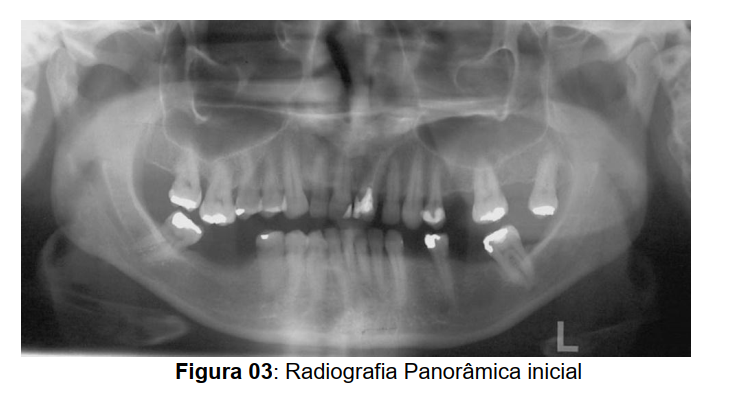

A paciente N. A. B. S., 30 anos, gênero feminino, procurou tratamento ortodôntico para intrusão do segmento posterior superior direito e esquerdo, que se encontravam-se extruídos devido à perda precoce dos elementos posteriores inferiores direito e esquerdo (Figura 1). Ao exame clínico constatouse que a mesma apresentava perfil reto com selamento labial passivo, sendo o tipo facial da paciente braquicefálico. Na análise de face a paciente apresentava o formato oval.

Na análise intrabucal, constatou-se que a paciente apresentava coincidência da linha média, má oclusão de classe I de caninos e trespasse vertical de 3mm e horizontal de 2mm. (Figura 02).

A paciente apresentava perda de dimensão vertical decorrente da perda dos elementos 46 e 36. Foi detectada ausência de espaço suficiente para a reabilitação protética posterior dos lados esquerdo e direito, sendo necessária a intrusão dos elementos 16 e 26 para viabilizar a instalação de implantes osseo integrado de titânio nos hemiarcos inferiores esquerdo e

direito (Figura 03).